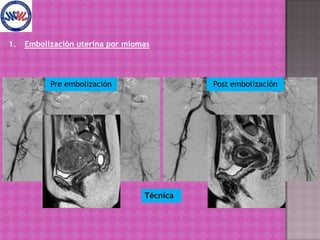

La embolización uterina por miomas fue desarrollada en Francia y su primera publicación internacional fue en 1995. Es un tratamiento seguro y eficaz, con bajas complicaciones y resultados comparables a la cirugía tradicional, con ciertas contraindicaciones absolutas y relativas. Se puede repetir y no impide futuras cirugías si es necesario.